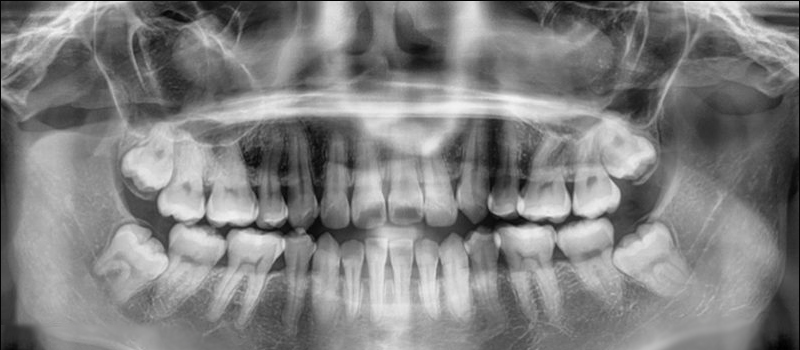

Many people suffer from teeth loss due to dental diseases, decay, cavities and injuries. Complete tooth loss is termed Edentulism, which results in an inability to chew food. Because food is not chewed properly, that …